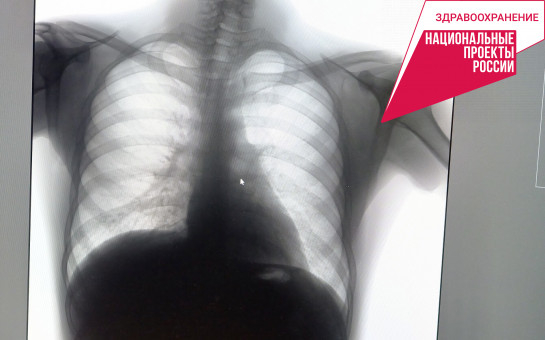

Заболеваемость туберкулезом в регионе снизилась на 23 процента

К таким выводам пришли фтизиатры, проанализировав данные по Новосибирской области за 9 месяцев. С начала года в Новосибирске и области зарегистрировано 37,7 случаев заражения туберкулезом на 100 тысяч населения. За тот же период 2022-го этот показатель был 47,1 на 100 тысяч. Снижение составило 23 %.

– Смертность от туберкулеза за те же 9 месяцев снизилась на 8,3 % и составила 5,5 на 100 тысяч населения. При этом охват диагностикой соответствует прошлогоднему. С января по сентябрь на туберкулез обследованы 56 % жителей Новосибирской области, – сообщили в пресс-службе минздрава НСО.

Главный фтизиатр региона Анна Пятибратова подчеркнула: в Новосибирской области заболеваемость туберкулезом снижается ежегодно, начиная с 2008 года, в среднем на 10 %.

– Эта тенденция сохраняется, во-первых, благодаря обеспечению фтизиатрической службы всеми необходимыми лекарственными препаратами. Второе – качественная доступная диагностика. 46 современных цифровых флюорографов получил наш регион по нацпроекту «Здравоохранение». В каждом районе Новосибирской области теперь есть собственный передвижной флюорограф, который выезжает в самые отдалённые населённые пункты. Ведётся большая совместная работа с инфекционистами, – отметила главный фтизиатр.

Фото с сайта минздрава НСО